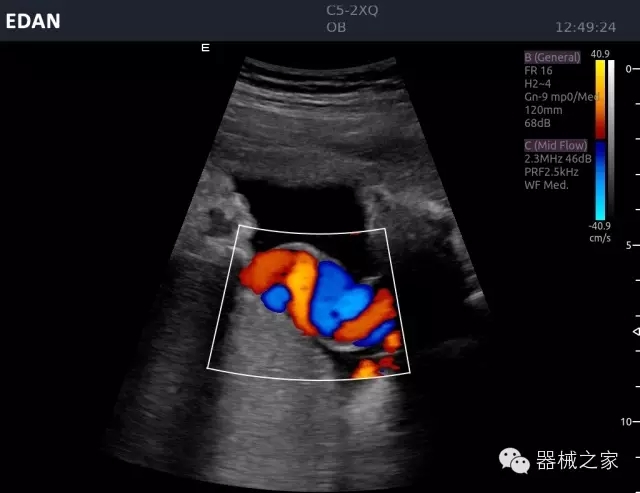

頸動脈頻譜